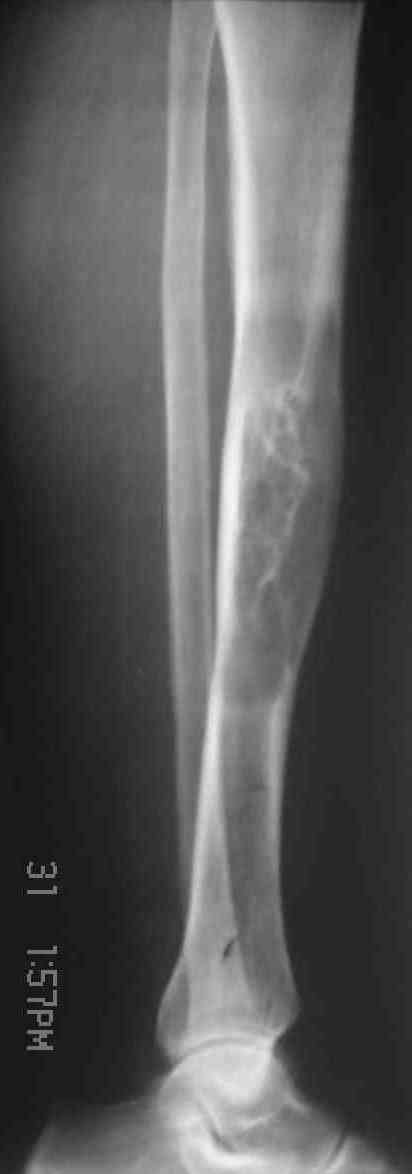

Я поддерживаю мнение доктора Odessky Jacob, что это образоавние возможно фиброзная дисплазия. Случай из моей практики - смотри рентгенснимки во вложении. Правда у моего пациента -полиосальная форма и болезнь проявилась в раннем детстве.

По представленным снимкам наиболее вероятен диагноз "фиброзная дисплазия".